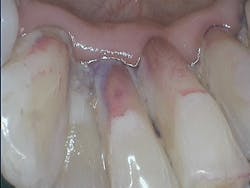

As clinicians, we should prevent scratching surfaces or creating mineral loss while removing biofilm, both of which could ultimately leave the surfaces more plaque- or stain-retentive. Flemmig et al. reminded clinicians in a 2007 study that “abrasion on tooth surfaces might become substantial over time, when the cumulative effects of repeated instrumentation during SPT [supportive periodontal therapy] are considered.”1

Another benefit of biofilm management via GBT is efficiency when implementing the eight-step system. Since clinicians remove biofilm from surfaces early on in the appointment, the need for overlapping, repetitive strokes using power or hand instrumentation is substantially reduced. Total debridement time is less, which allows extra time for additional services and patient education. The patient experiences less mechanical instrumentation with GBT, yet enjoys the optimal outcome of smooth, clean surfaces.

Integration of technologies that save time during the appointment, are safe and comfortable for the patient, and are easy for clinicians to use have multiple benefits—from increased longevity for the practicing clinician, to increased referrals from pleasant patient experiences, to confidence in “doing no harm” on delicate oral surfaces during biofilm removal.